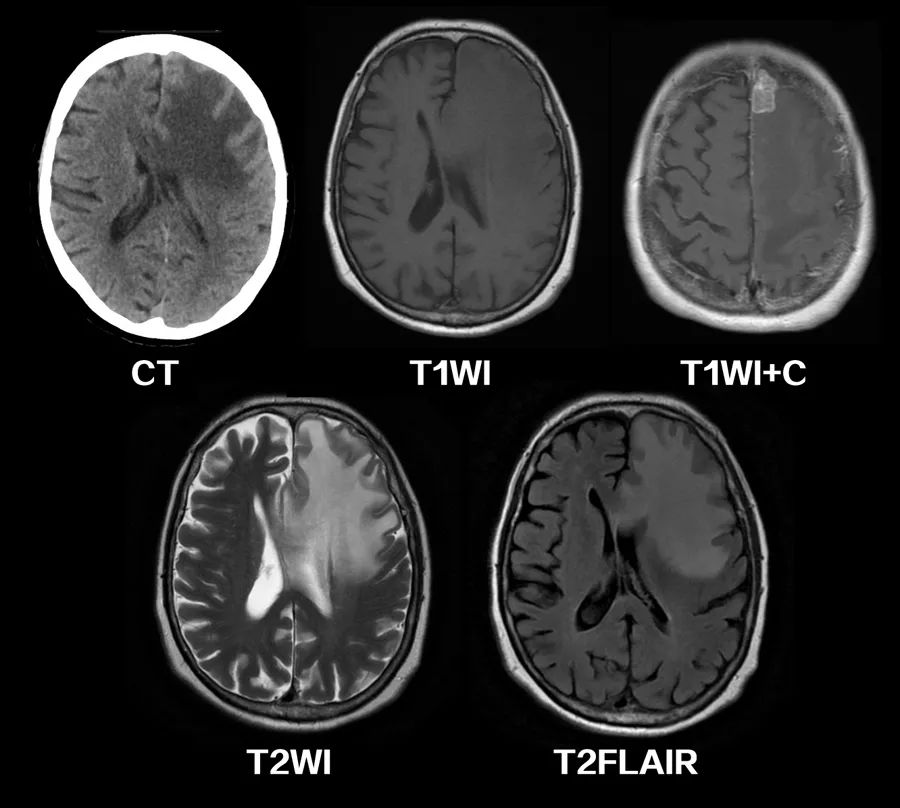

图3 40岁女性,脑脓肿,T2FLAIR像上可见病灶周围片状高信号区域,并呈手指状向周围延伸。

图4 乳腺癌脑转移,CT、MRI上可见广泛的血管源性脑水肿区域,侧脑室受压,中线移位。引起血管源性脑水肿的占位性病变位于左额上回。